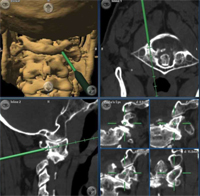

Las fijaciones vertebrales posteriores mediante el implante de tornillos es un acto delicado y de riesgo, de aquí que estos pacientes sean tratados en centros específicos. El Dr. Florensa tiene una larga experiencia en el tratamiento de estos pacientes acreditada en diferentes publicaciones científicas.

Dichas fijaciones posteriores las realizamos mediante cirugía guiada con navegador y monitorización intra-operatoria con excelentes resultados.